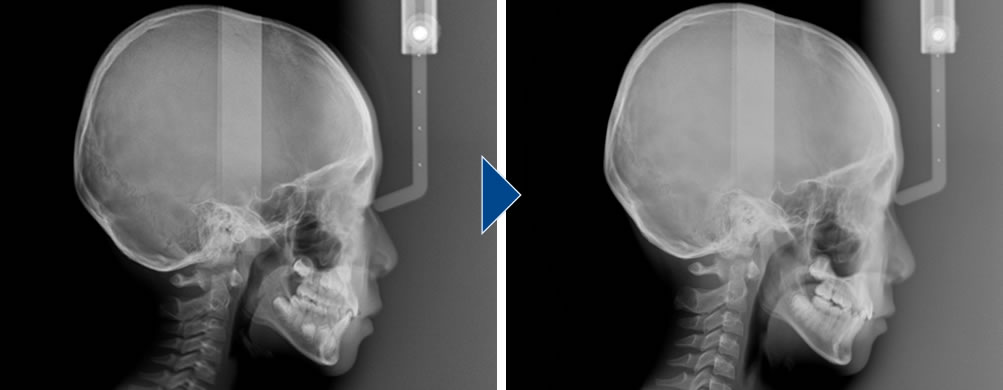

治療前後のセファロレントゲン画像です。治療前に比べて僅かですが、上顎が前に出ています。早い段階で小児矯正を行うことで、負担を抑えて骨格の問題も改善することができます。